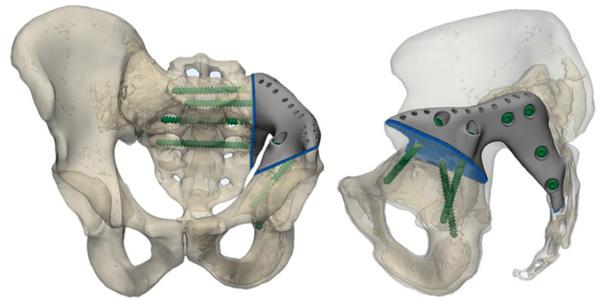

Рафаэль прошел несколько циклов полихимиотерапии, что позволило добиться стабилизации состояния. Одновременно с проведением химиотерапевтического лечения началось проектирование индивидуального эндопротеза с использованием 3D-принтинговых технологий. Из-за нестандартной резекции на этапе предоперационного планирования сначала был создан макет таза и эндопротеза. Затем методом послойного лазерного плавления титанового порошка на 3D-принтере в петербургской компании «Остконнект» был изготовлен имплант.

В конце марта 2020 года была выполнена сложнейшая операция по резекции левой подвздошной кости и крестца с одномоментным протезированием индивидуальным 3D-принтинговым эндопротезом.